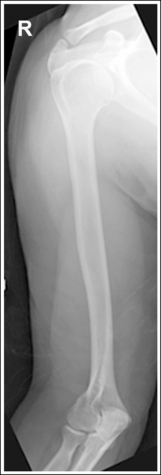

Scatter radiation is controlled. Image density is uniform across the humerus.

• If the patient's upper arm AP thickness measures less than 4 inches (10 cm), a grid is not required. For such a patient, a high-contrast, low-kVp (below 60) technique sufficiently penetrates the bony and soft tissue structures of the humerus without causing excessive scatter radiation to reach the IR and hinder image contrast. If the upper arm measures more than 4 inches (10 cm), a grid should be used, because this thickness would produce enough scatter radiation to affect the image contrast negatively. When a grid is used, increase the kVp to above 70 to penetrate the thicker humerus and provide an adequate scale of contrast. If the technique is manually set, increase the exposure (mAs) by the standard density conversion factor for the grid ratio (number used to express a grid's scatter-eliminating ability) being used to compensate for the scatter and the primary radiation that the grid will absorb.

• Anode heel effect. To take advantage of the anode heel effect, position the thinner elbow (distal humerus) at the anode end of the tube and the thicker (proximal humerus) at the cathode end. Set an exposure (mAs) that will adequately demonstrate the midpoint of the humerus.

The humerus is in an AP projection. The medial and lateral humeral epicondyles are demonstrated in profile, and the radial head and tuberosity are superimposed over the lateral aspect of the proximal ulna by approximately 0.25 inch (0.6 cm). The greater tubercle is demonstrated in profile laterally, the humeral head is demonstrated medially in profile, and the vertical cortical margin of the lesser tubercle is visible approximately halfway between the greater tubercle and the humeral head.

• An AP projection is obtained by placing the patient in a supine or upright AP projection, with the affected arm extended. Supinate the hand and externally rotate the elbow until an imaginary line drawn between the palpable humeral epicondyles is aligned parallel with the IR (Figure 4-88). This positioning places the proximal radius anterior to the ulna, causing the radial head and tuberosity to be superimposed over the lateral ulna by approximately 0.25 inch (0.6 cm), and places the greater tuberosity in profile.